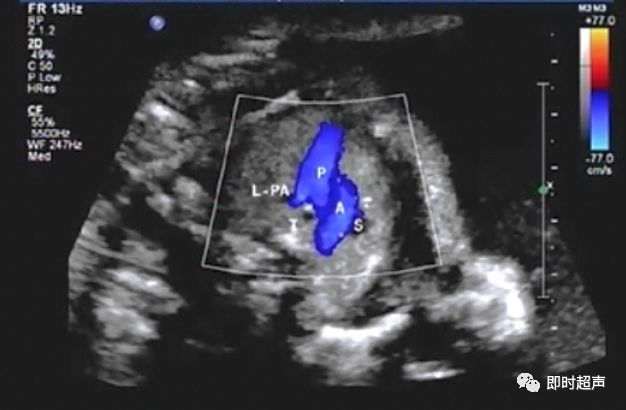

肺动脉血流反向

右心发育不良综合症(三尖瓣或肺动脉瓣闭锁或重度狭窄)

肺动脉内径正常能否除外肺动脉瓣闭锁或狭窄?——不能

肺动脉瓣闭锁时肺动脉是否一定变细?

- 肺动脉不一定变细,因为肺动脉的血液是由主动脉经动脉导管来反向灌注的,只要动脉导管足够粗,肺动脉内径是可以不变细的。

- 但肺动脉的血流方向一定是和主动脉相反的。

- 所以诊断时不能依靠肺动脉的内径来判断有无肺动脉瓣闭锁。